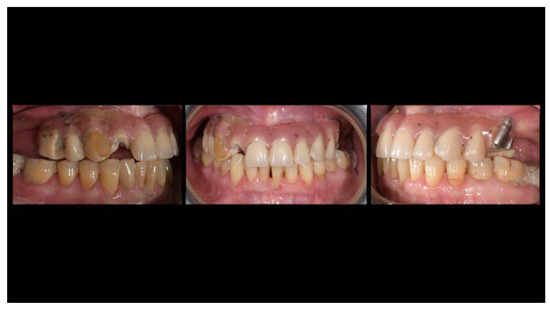

A partially edentulous 78-year-old woman with a complete screw-retained implant-support hybrid prosthesis (Figure 1) in the upper jaw and natural dentition in the lower jaw was referred to a private center in Rome, Italy, due to several continuous breakages of the prosthetic part of the implant-supported rehabilitation. After a preliminary interview, the patient stated that the implant treatment was finished two years before, but she had never been comfortable with this prosthesis (Figure 2). Relevant symptoms were phonetic difficulties, inability to maintain hygiene, and repeated breakages, leading to functional and esthetic issues (Figure 3). After that, the patient’s medical history was collected, and preoperative photographs, radiographs, periodontal screening results, and model casts were obtained for initial evaluation (Figure 4). During the clinical examination, the actual prosthesis was unscrewed, due to teeth detachments, and replaced with the old temporary prosthesis delivered by the patient. Both existing prostheses were evaluated and judged inaccurate, with particular attention to the fit of the prosthesis, the vertical dimension of occlusion, phonetics, facial support, and lip position. All the possible treatment options were then discussed and evaluated together with the patient. The main concerns of maintaining the previously placed implants were some exposed threads and the troubling disparallelism that makes the prosthetic treatment difficult, increasing the risk for biological complications and technical complications, respectively (Figure 5). Nevertheless, the patient refused a complete removable denture, so that implant removal would lead to placement of new implants, in combination with guided bone reconstruction and soft tissue management. This treatment plan may have the risks of implant failure and increased patient morbidity (Table 1 and Table 2). An implant-supported fixed dental prosthesis was initially excluded due to the implant’s disparallelism. Hence, a maxillary implant-supported overdenture was initially considered quite possibly the best therapeutic option.

Figure 1.

Picture of the patient’s work and initial situation.

Figure 2.

Pictures of detachments of tooth parts and pink resin from the prosthetic restoration.